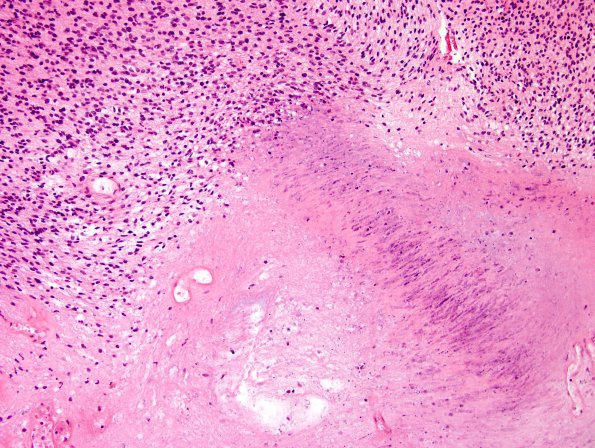

Washington University Experience | NEOPLASMS - CRANIAL AND PARASPINAL NERVEs | Schwannoma | 21B4 Schwannoma, 12yo girl (Case 21) H&E 5.jpg

Evolving infarct-like necrosis is multifocal but does not preferentially occur in hypercellular regions, as might be seen in malignant necrosis. Tumor cytology is low-grade and mitotic activity is rare.